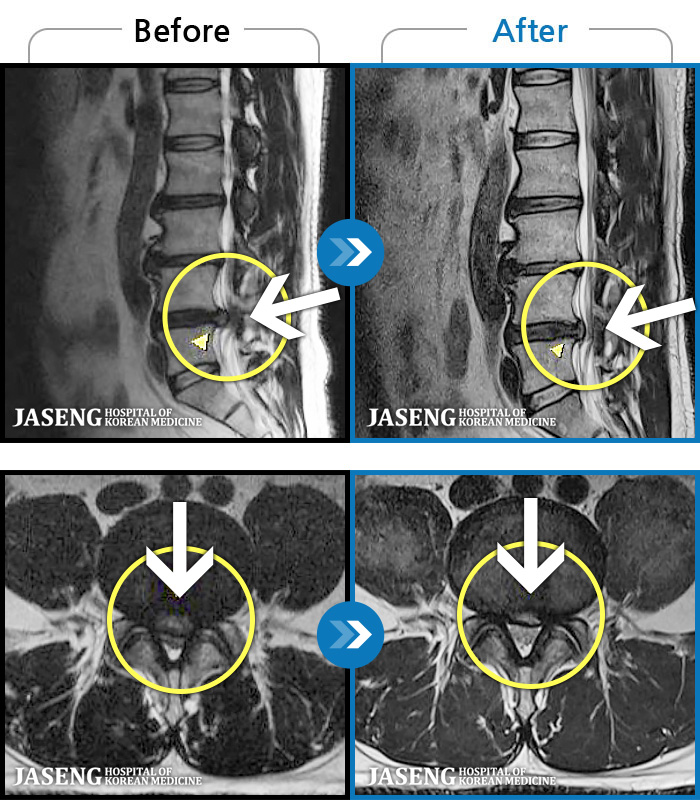

MRI ġ

1,240 MRI ũ ʸ Ȯϼ.